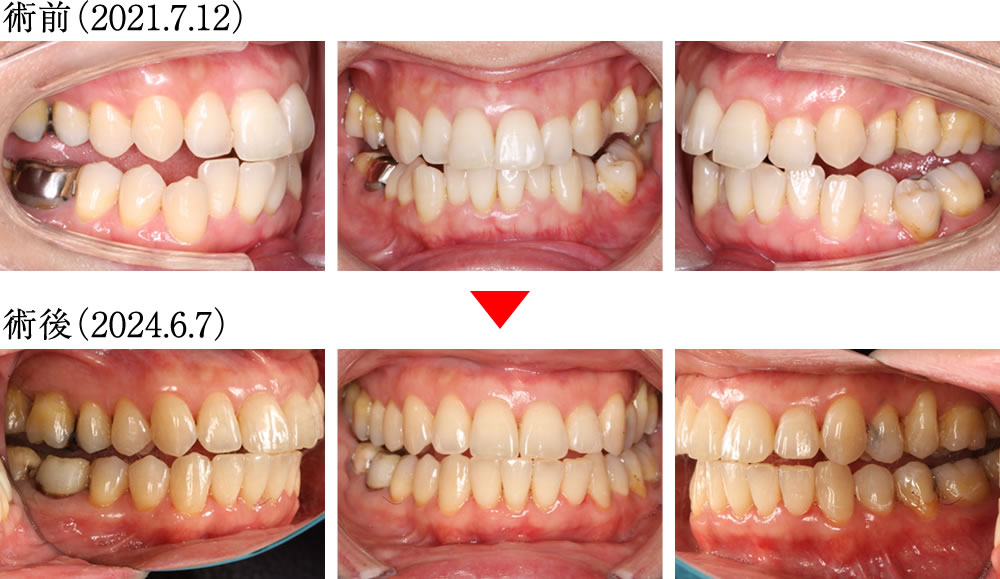

術前は下顎を動かした際に犬歯が全く機能しておらず、不安定な噛み合わせでしたが、術後は前歯と犬歯が正常に機能するようになり、安定した理想的な咬合へと改善されました。